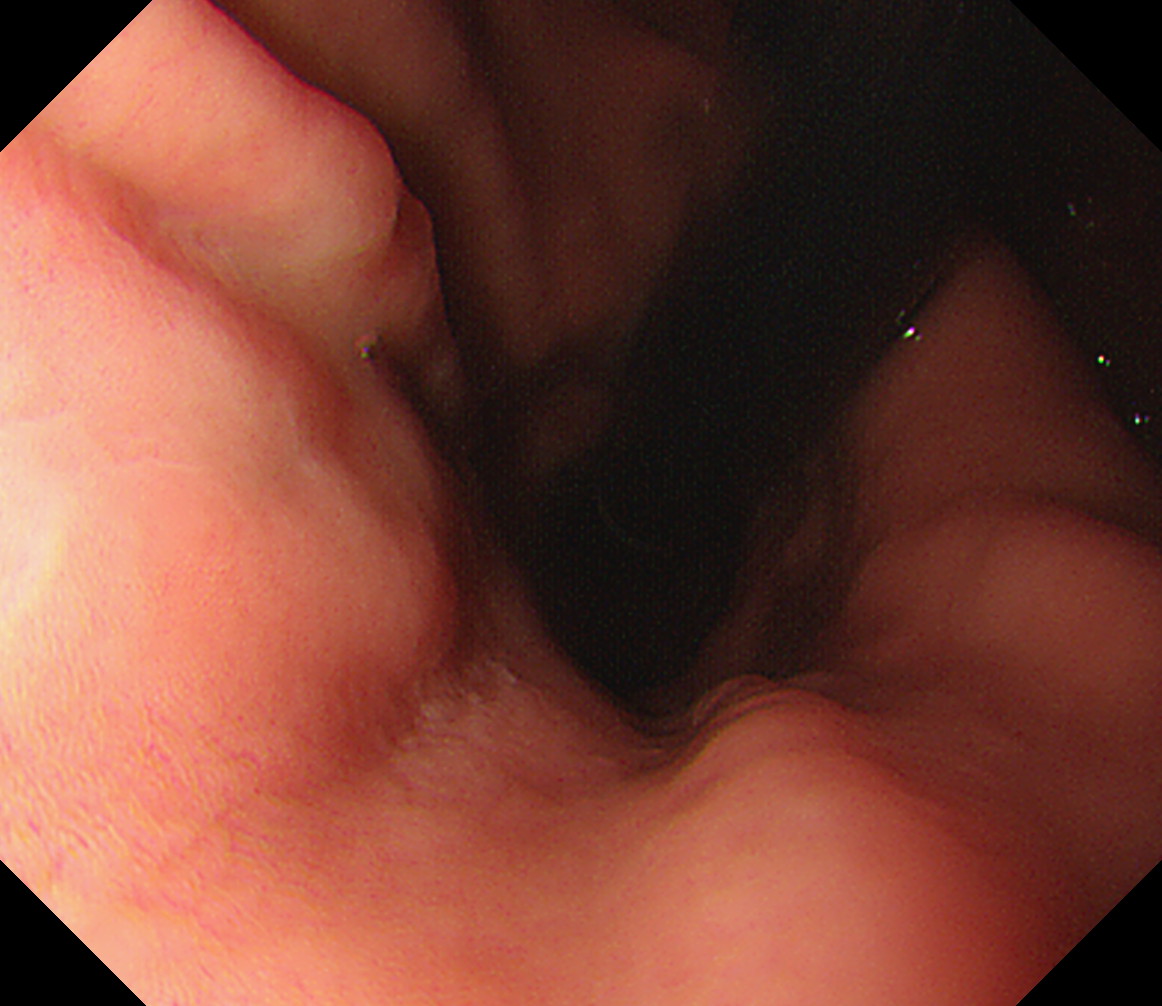

3 EGJ この人はLos-Angeles分類 GradeDの逆流性食道炎があります。 EGJ

8 幽門輪 いわゆる「PーRing」 幽門輪

14 体下部小弯(角上部) [J反転]して以降見上げです 体下部小弯(角上部)